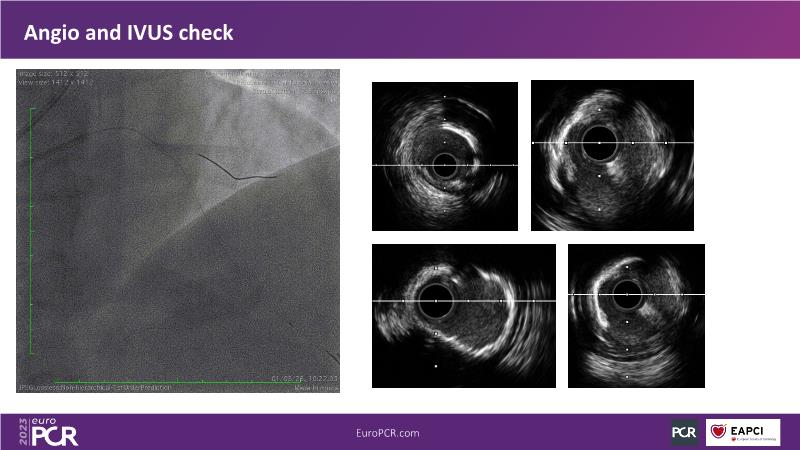

• To understand why you can count on customised drug delivery platform of DES+DCB in complex settings with imaging-based evidence through case presentations